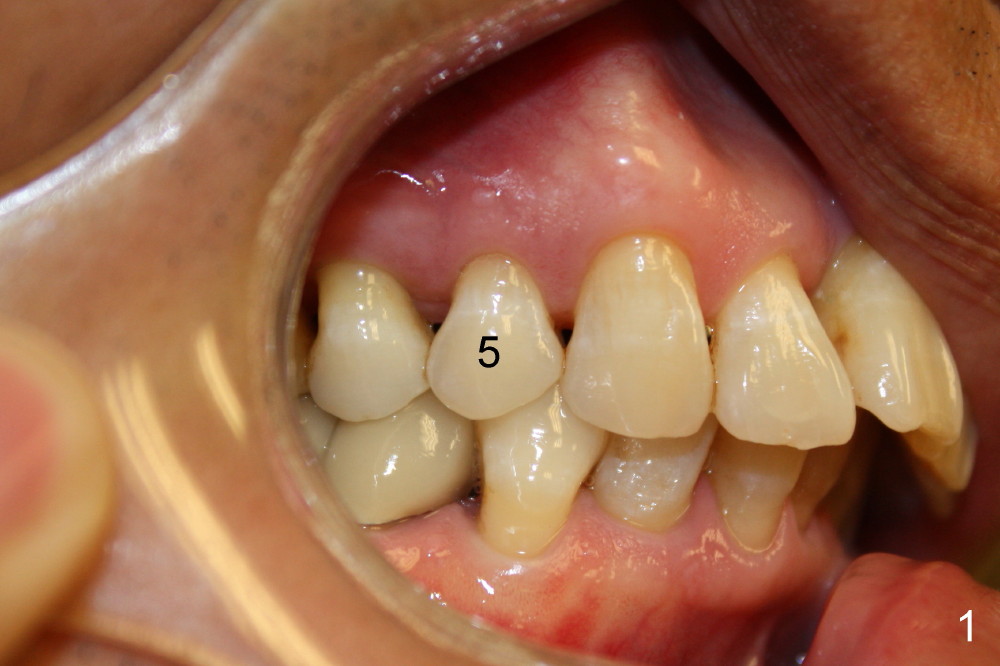

A 56-year-old man fractures the lingual cusp of the upper right 1st premolar (Fig.1,2).

A provisional is fabricated immediately after extraction and implant and definitive abutment placement (Fig.3,4: P). The provisional hold the papilla in place (Fig.3 *). There is no occlusal contact with the opposing dentition (Fig.4 ^). The gingiva looks purplish due to difficult extraction. The tooth keeps fracturing while being extraction. The bone is dense. On the other hand, the dense bone helps achieve primary stability of the implant.

The patient returns 6 months postop for impression of a permanent restoration. The gingiva with knife-edged papillae adapts to the provisional (Fig.7). The gingiva looks healthy when the provisional is removed (Fig.8). The buccal bone resorption seems to be minimal, as compared to Fig.1,2. There is no bone loss between immediately postop (Fig.9 I; implant), 4.5 months postop (Fig.10 A: abutment), 4 and 7 months post cementation (Fig.11,12 C: crown). Soft and hard tissue morphology remains normal 7 months post cementation (Fig.13). No bone loss is observed 15 months post cementation (Fig.14). The papillae (Fig.15) and bone (Fig.16,17) remain stable 29 months post cementation.